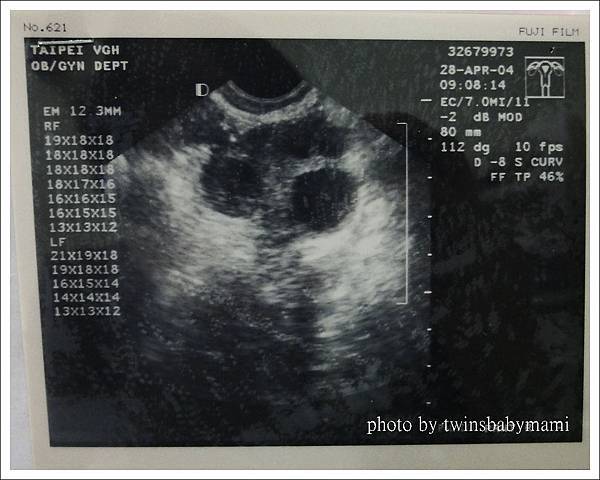

內診陰超看診中,

莊醫生眉頭深鎖的說「奇怪了,排卵藥的劑量已經提高了,怎麼卵子還是都不夠大!」

莊醫生「妳老婆的卵子還是不夠成熟、不夠大!」